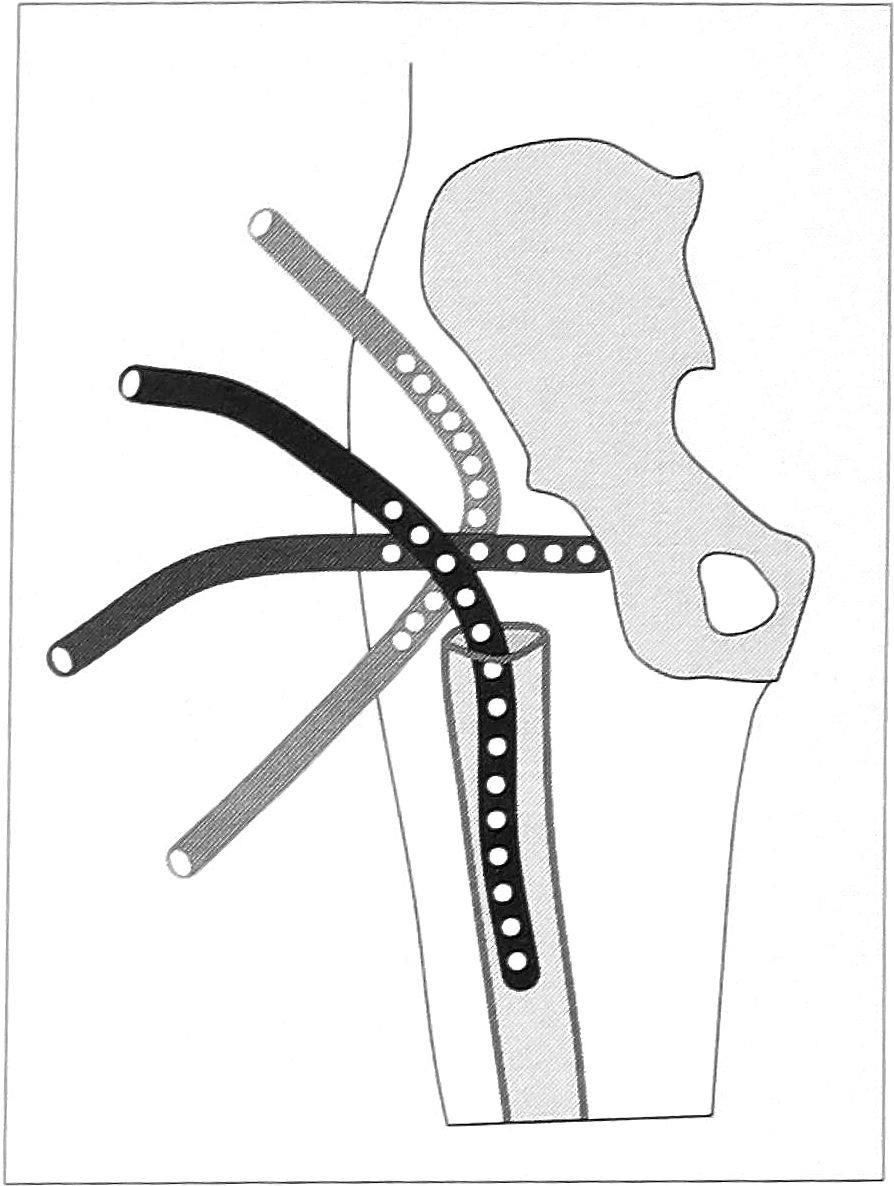

По завершении этого этапа операции меняли операционное белье и хирургические инструменты. Оперируемую конечность отводили до угла 45°, укладывали на дополнительный стерильный стол, стопу фиксировали в функционально правильной нейтральной позиции. В случаях, когда удалялся нагноившийся эндопротез, обязательно выполняли однополюсное дренирование костномозгового канала и области вертлужной впадины. Кроме того, проводили двухполюсную трубку по всей длине послеоперационной раны в продольном направлении под мышцами, после чего их ушивали (рис. 5).

Рис. 5. Схема системы ирригационного дренирования раны после операции с удалением эндопротеза.

Если в ходе операции костномозговой канал не вскрывался, рану дренировали двумя дренажами: в том же направлении над ушитыми мышцами проводили еще один двухполюсный дренаж. После завершения операции ногу фиксировали в деротационной шине с ранее приданной ей установкой отведения и нейтральной ротации.